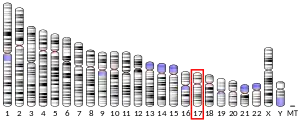

Amine oxidase, copper containing 3 (AOC3), also known as vascular adhesion protein (VAP-1) and HPAO is an enzyme that in humans is encoded by the AOC3 gene on chromosome 17. This protein is a member of the semicarbazide-sensitive amine oxidase (SSAO; aka primary amine oxidase) family of enzymes and is associated with many vascular diseases.[5]

VAP-1 is a type 1 membrane-bound glycoprotein that has a distal adhesion domain and an enzymatically active amine oxidase site outside of the membrane.[6][7] The AOC3 gene is mapped onto 17q21 and has an exon count of 6.[5]